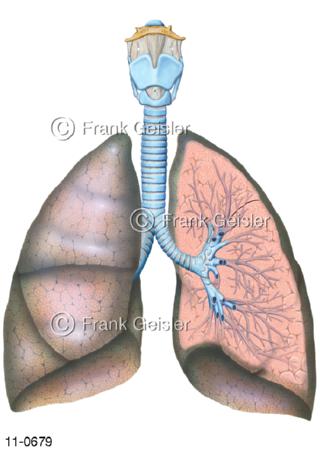

11-0679 Kehlkopf Luftröhre Bronchien Lunge, links eröffnet